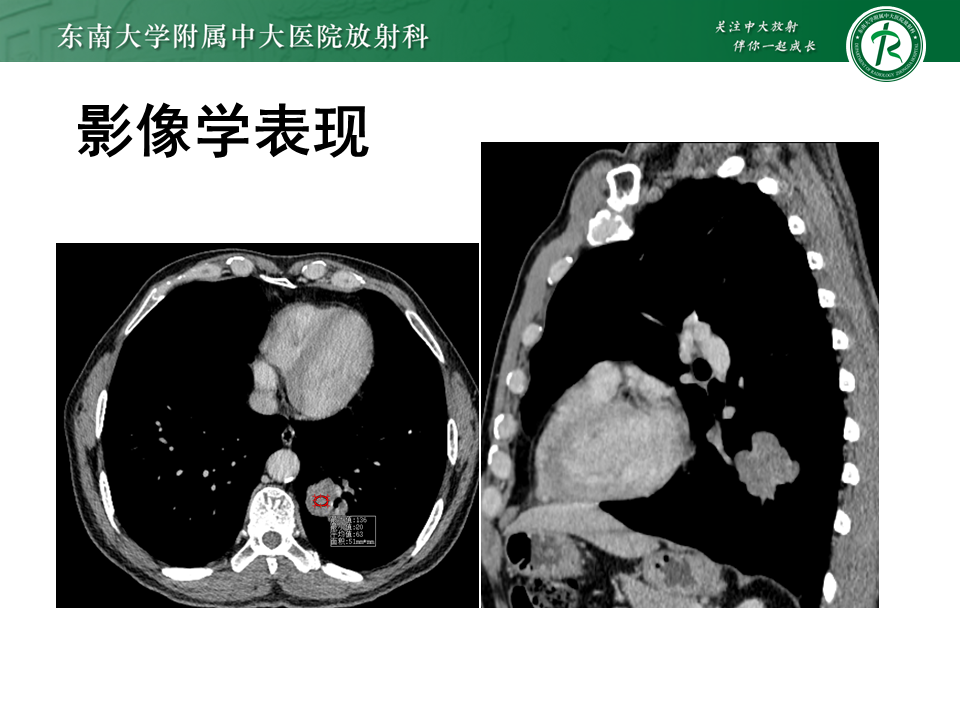

• 影像学检查:3536585,2025-11-10 胸部CT增强

影像学表现

图片来源:东南大学附属中大医院放射科